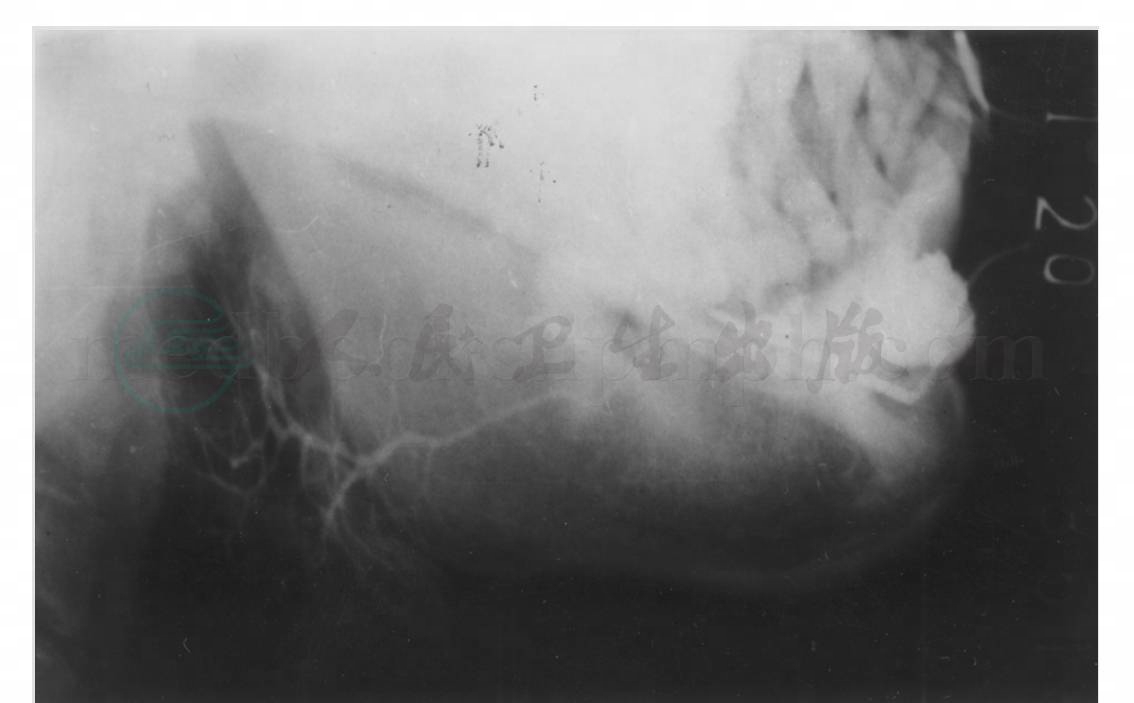

2. 颌下腺造影侧位片

颌下腺导管口位于舌下区前部,主导管长5~7cm,管径2~4mm,由前上向后下行经下颌体部。腺体外形近似梨形,显像于颌下部软组织中,约在下颌角前下方向两侧分出分支导管。颌下腺也可有副腺体,在接近颌下腺腺门处分出,大多在主导管下部(图2)。

图2 正常颌下腺造影